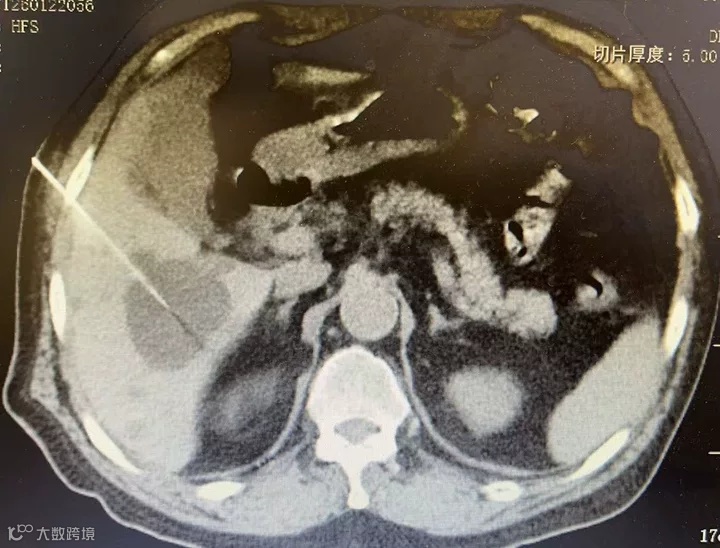

近日,我院呼吸介入团队在有着数十年介入诊疗经验的科室业务主任成佳科带领下,成功为一名体检发现多发肝囊肿的患者实施了CT引导下肝囊肿穿刺聚桂醇硬化治疗术。手术全程严格遵循《多脏器囊肿硬化治疗中国专家共识》规范,患者术后恢复平稳,标志着我院介入技术在跨病种治疗上稳定发挥。

术前,科室团队结合患者影像资料进行了细致评估,精准规划了穿刺路径。术中在CT实时引导下,穿刺针准确抵达目标位置,成功抽吸囊液并完成冲洗。随后,经造影确认位置无误后,注入硬化剂并保留。术后复查显示囊肿已基本消失,手术取得预期效果。整个流程平稳有序,以微创方式为患者解除了病痛。